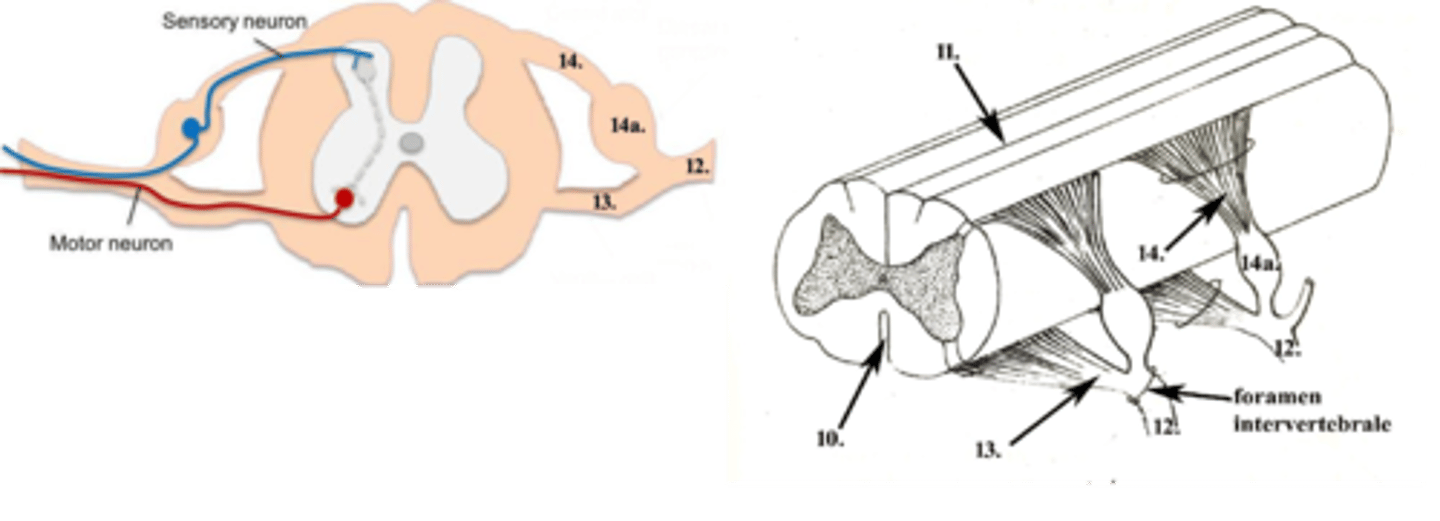

fissura mediana

10

sulcus medianus

11

nervi spinales

12

radix ventralis

13

radix dorsalis

14

ganglion spinale

14a